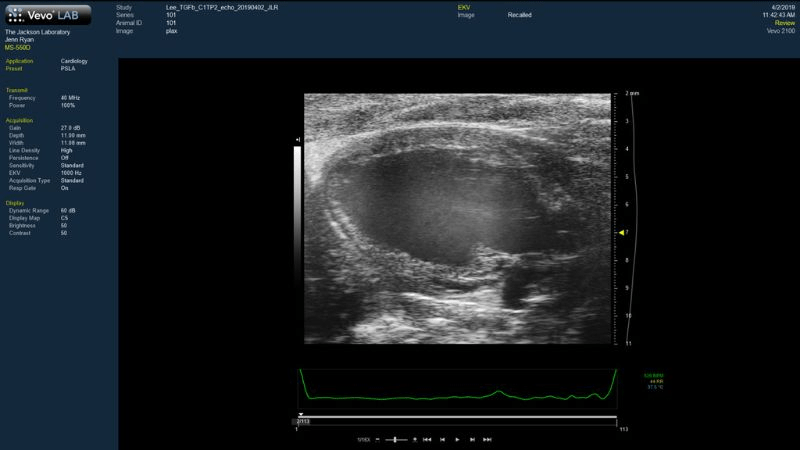

PCP Electroretinography | PCI Ultrasonography |